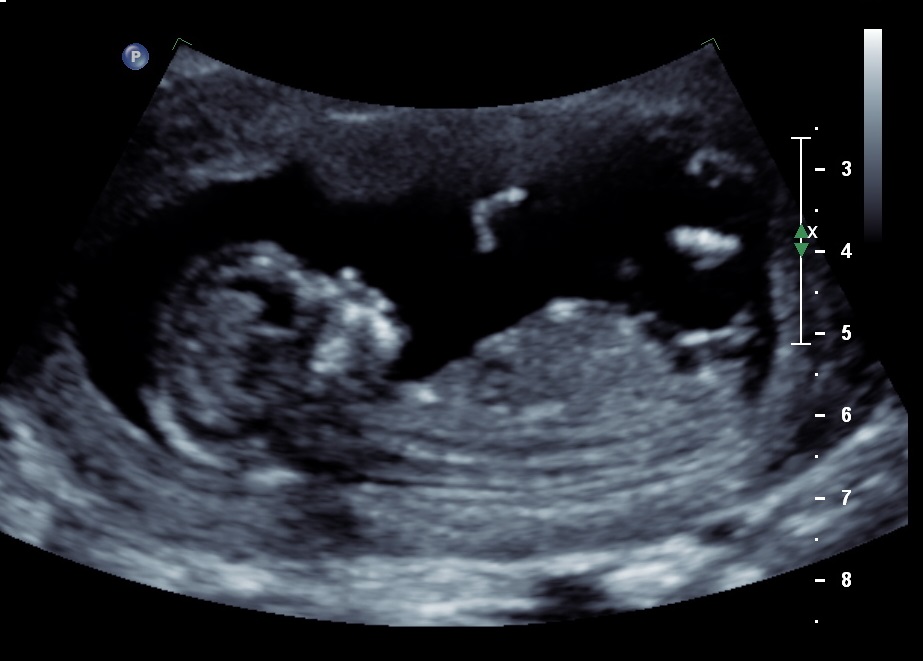

Please help! I am rubbish at reading ultrasounds! Can anyone see the nub and read it for me please? My friend thought she saw it and thought it was a boy angle....but my gut says girl. Hubby isn't letting me find out at the 20w scan so this is the only clue I get!! Thanks so so much.

I'm 12w3d by dates, 13w3d by scan.